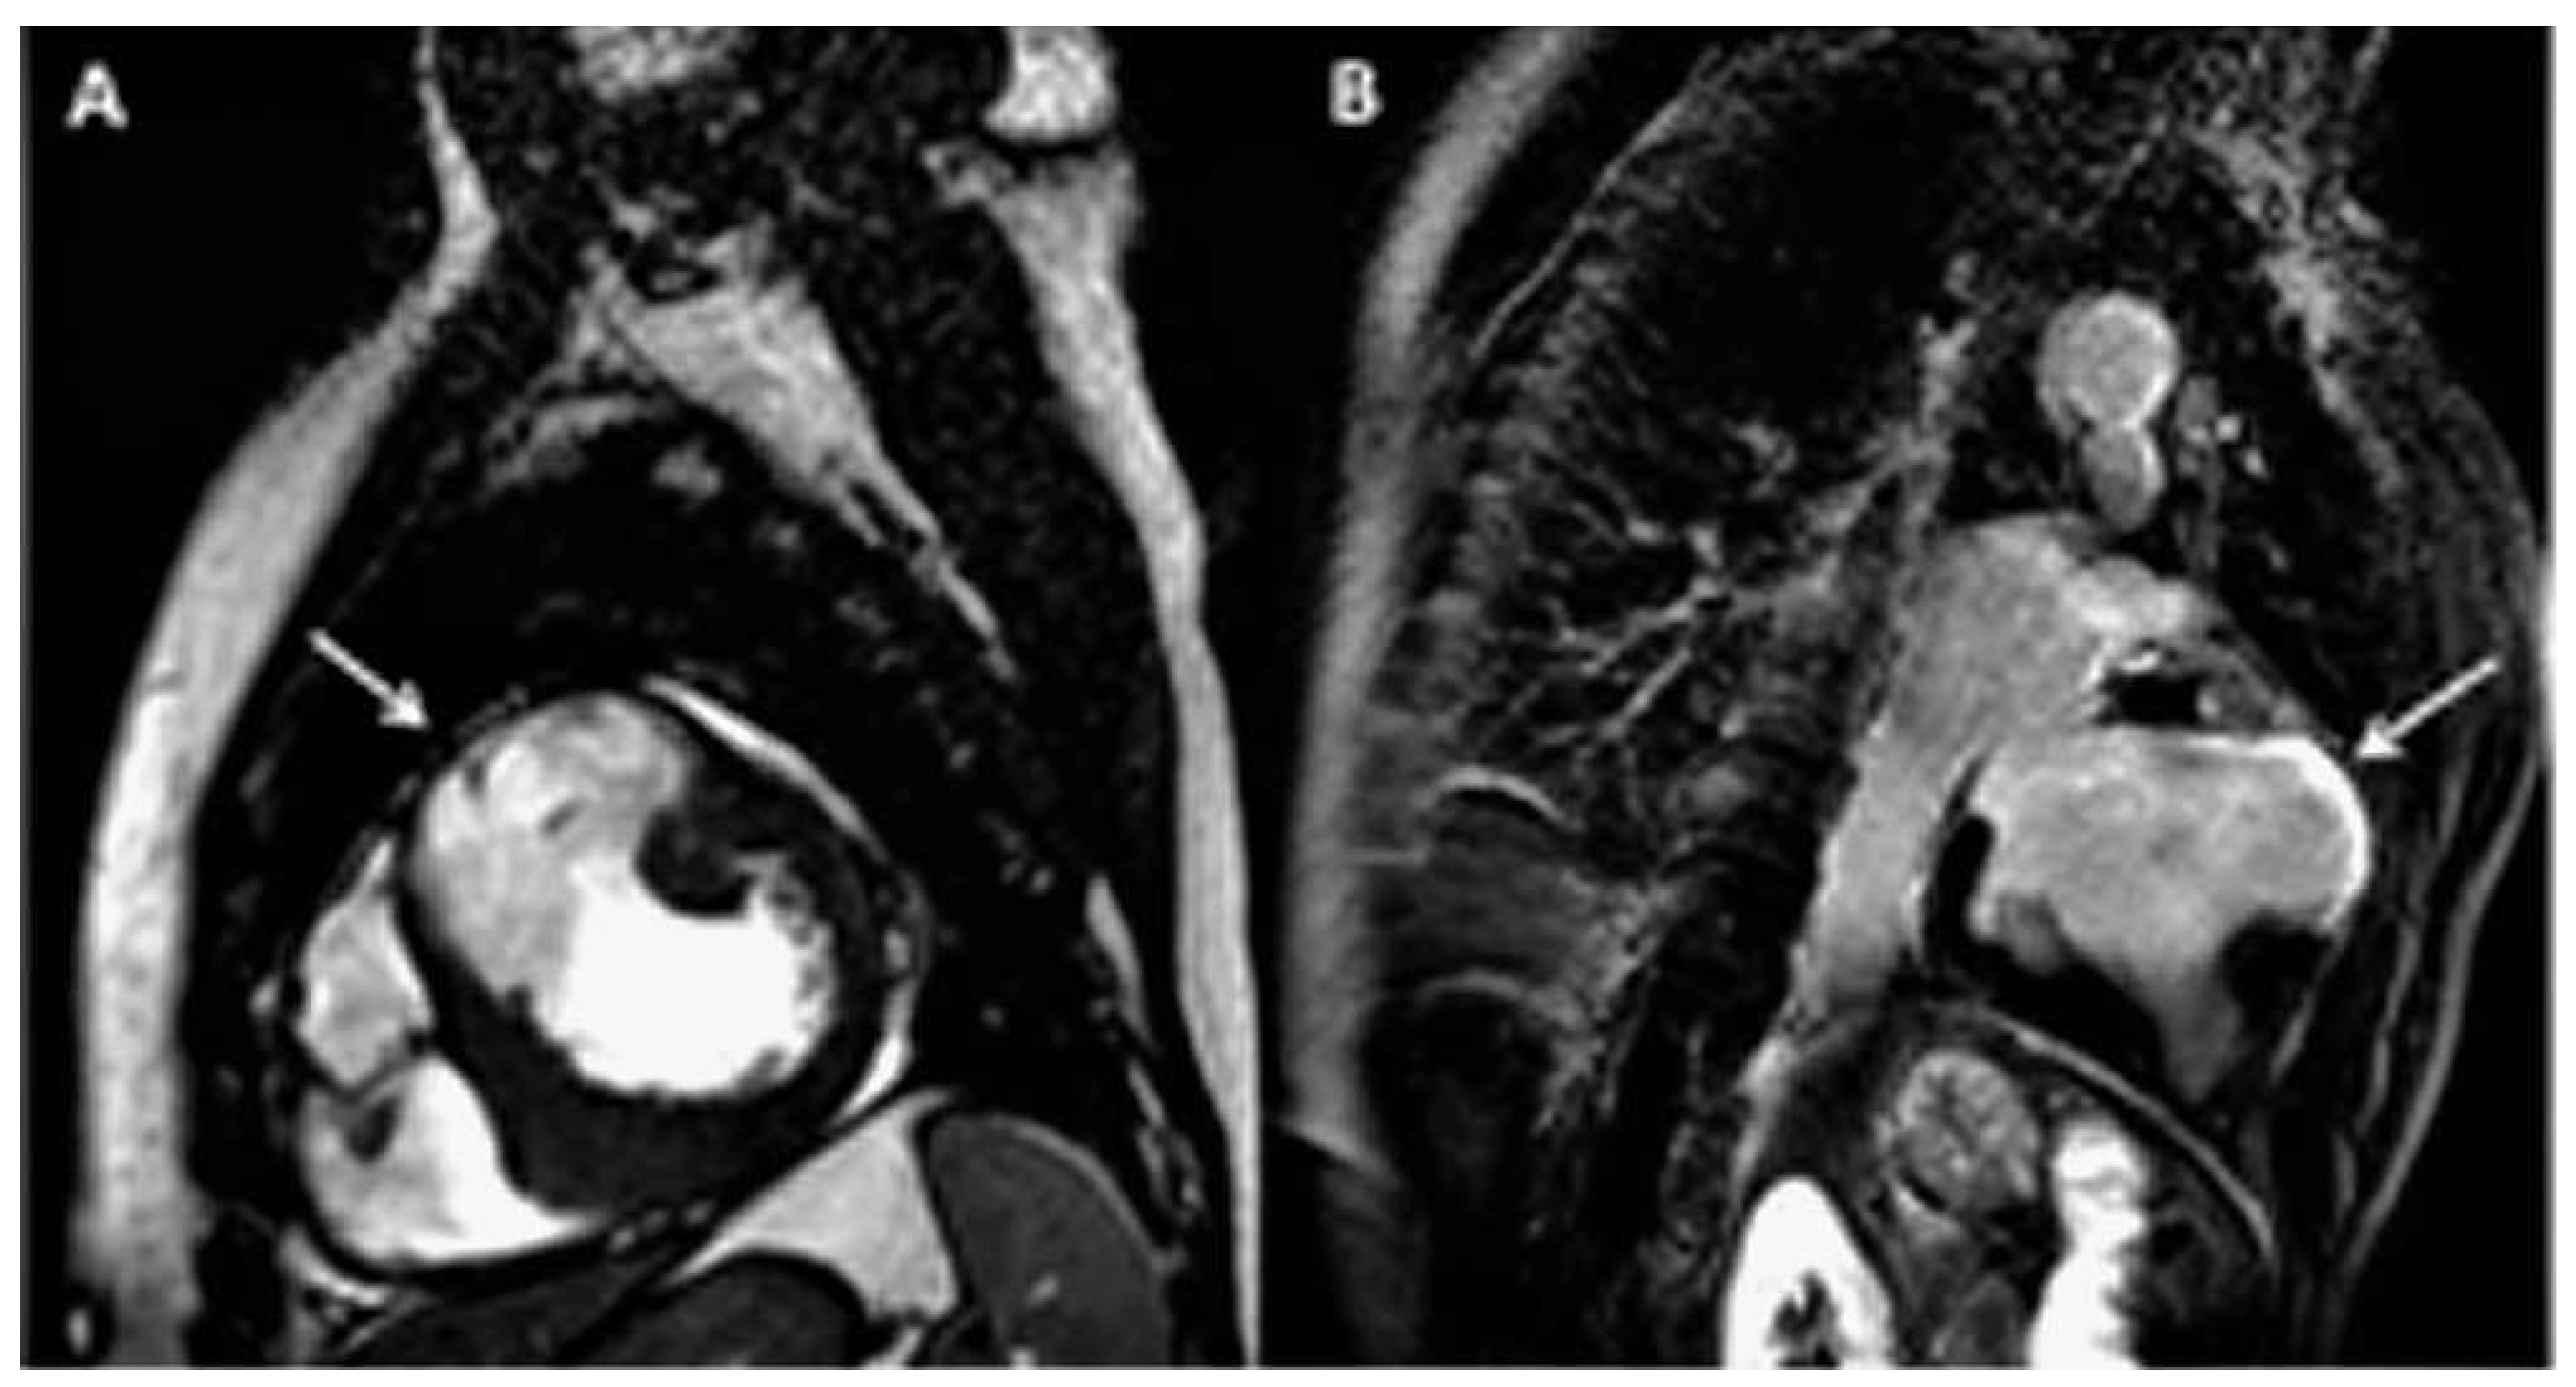

Magnetic resonance imaging (MRI) was performed to search for the possible explanations of the nature of the aneurysm. It showed transmural late gadolinium enhancement (LGE) of the entire akynetic aneurysmal wall, consistent with transmural scar (Figure 2A,B, arrows).

Figure 2. Cardiac MRI sagittal view showing the thinning of the wall of the aneurysm (A, arrow) and the presence of transmural late gadolinium enhancement (B, arrow).